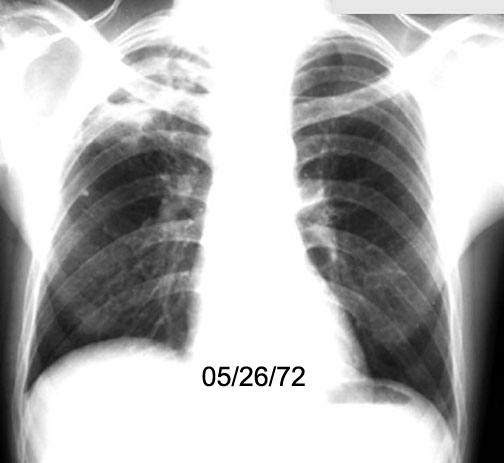

Case 8

Lateral

Follow up

Labeled Image I treated this patient as having lung abscess secondary to aspirated coin. The cavity turned out to be due lung cancer.

Moral: Close follow up until the problem is resolved.